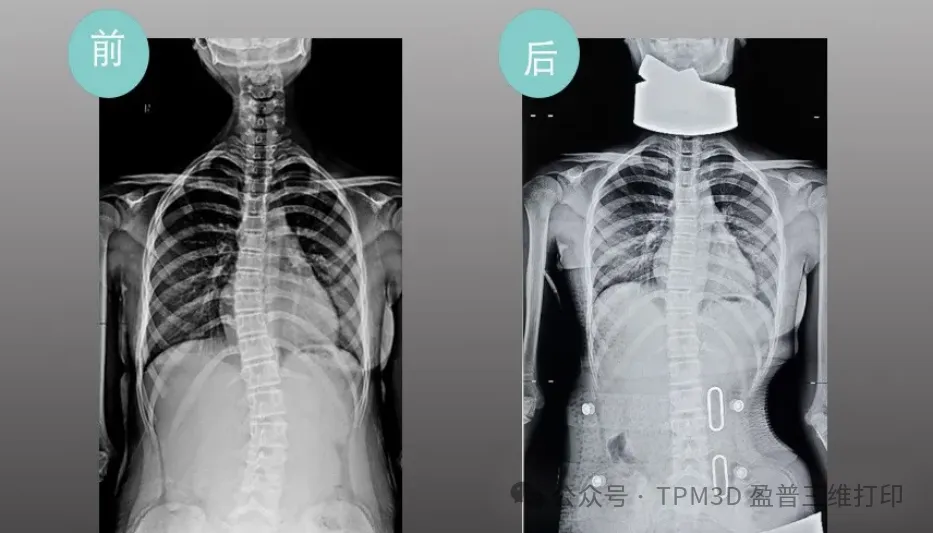

中心曾接診過這樣一位患者--五年級的小羅。當時,她因 25°脊柱側彎面臨治療困境,家庭經濟壓力更讓她的矯正之路舉步維艱。得知情況后,盈普技術團隊與中心迅速聯動,為小羅定制了專屬的 3D 打印矯形支具。從數據采集、支具設計到打印成型,全程僅用很短時間便完成。

令人欣喜的是,小羅佩戴支具僅一周,脊柱側彎度數就從 25°降至 10°以內。如今的她,身姿挺拔,重拾自信,家屬特意送來錦旗,上面 “仁心仁術治側彎”的話語,是對這份科技與醫療結合的溫暖最生動的注解。